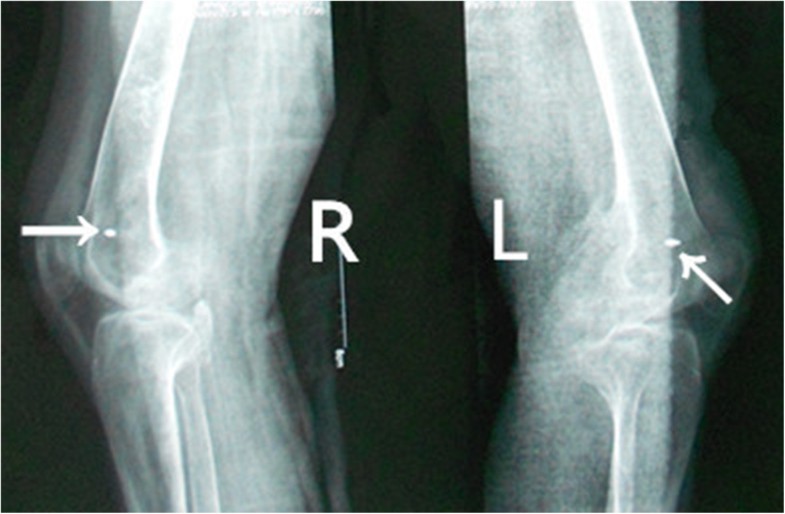

Bilateral genu varum deformity correction in an adult by medial opening Case Report On Knee Pain Here, we report a case of preliminary research to study the potential of core muscle training on alterations of core muscle. Mrs patell is a 64 year old woman with osteoarthritis of the right knee. The pain produced by oa of the knee is more intense during a period of. Reports of complex regional pain syndrome involving primarily knee have. Case Report On Knee Pain.